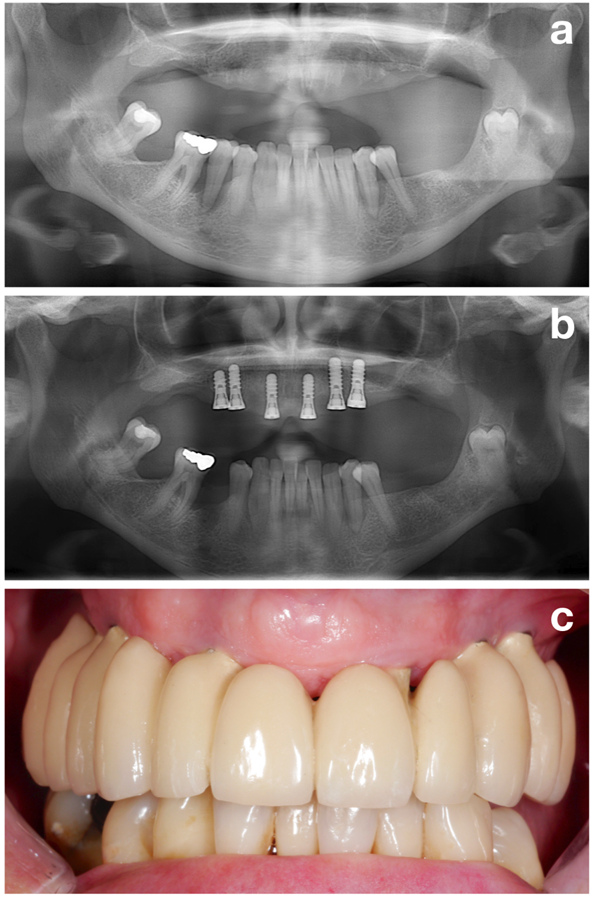

Il concetto NIWOP (Figura 1) è suddiviso in 3 aspetti principali: (1) fase di pre-trattamento, (2) inserimento dell'impianto e (3) richiamo o trattamento di supporto.

La prima parte (ossia, la fase di pre-trattamento) mira a preparare perfettamente il paziente per l'effettivo inserimento dell'impianto valutando tutti i potenziali fattori di rischio ma focalizzandosi su uno dei più importanti: l'ottenimento di una situazione parodontale stabile (Figura 2).

In conclusione, l'ottenimento di una situazione parodontale stabile è, insieme ad altri obiettivi, quali smettere di fumare o una perfetta igiene orale (Figura 3), uno dei più importanti obbiettivi della fase di pre-trattamento, e dovrebbe essere raggiunto prima di inserire l'impianto.